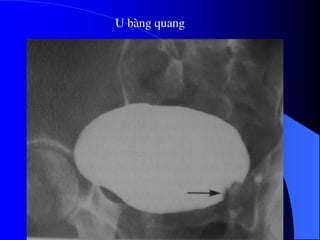

U bµng quang

- NÂTM + Âäúivåïi thãø thám nhiãùm coï hçnh aính heûp, båì khäng âãöu, thæåìng gáy æï næåïc. + Âäúi våïi thãø suìi, coï hçnh khuyãút saïng trong âæåìng dáùn niãûu, båì coï thãø khäng âãöu, coï thãø gáy æï næåïc âæåìng dáùn niãûu phêa trãn. Cáön phán biãût våïi cuûc maïu âäng vaì soíi KCQ. ٠Soíi vaì maïu cuûc di chuyãøn vë trê, coï viãön caín quang bao quanh. ٠Maïu cuûc thay âäùi hçnh daûng theo thåìi gian. ٠U âæåìng dáùn niãûu (bãø tháûn, niãûu quaín, baìng quang) coï hçnh aính chán baïm vaìo thaình, nåi khäng coï viãön TCQ bao quanh u.

- Siãu ám Khoïcháøn âoaïn u bãø tháûn, niãûu quaín nãúu khäng coï æï næåïc âaìi bãø tháûn niãûu quaín. U baìng quang trãn siãu ám tháúy hçnh tàng ám trong baìng quang coï næåïc tiãøu räùng ám. Siãu ám coï thãø tháúy mæïc âäü xám láún thaình baìng quang vaì ngoaìi thaình baìng quang.